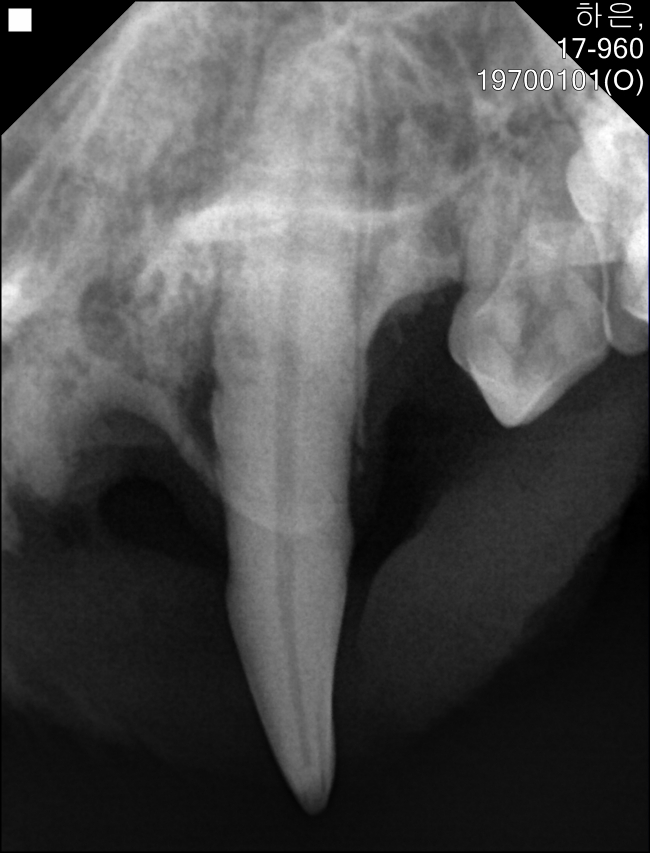

아래 앞니 엑스레이입니다.